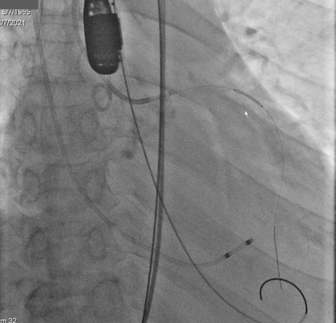

手术影像记录:

植入前冠脉造影

主动脉根部造影

直头导丝跨瓣

20mm球囊预扩

冠脉保护支架植入

AV23瓣膜释放到工作位

瓣膜完全释放

冠脉支架释放

植入后造影